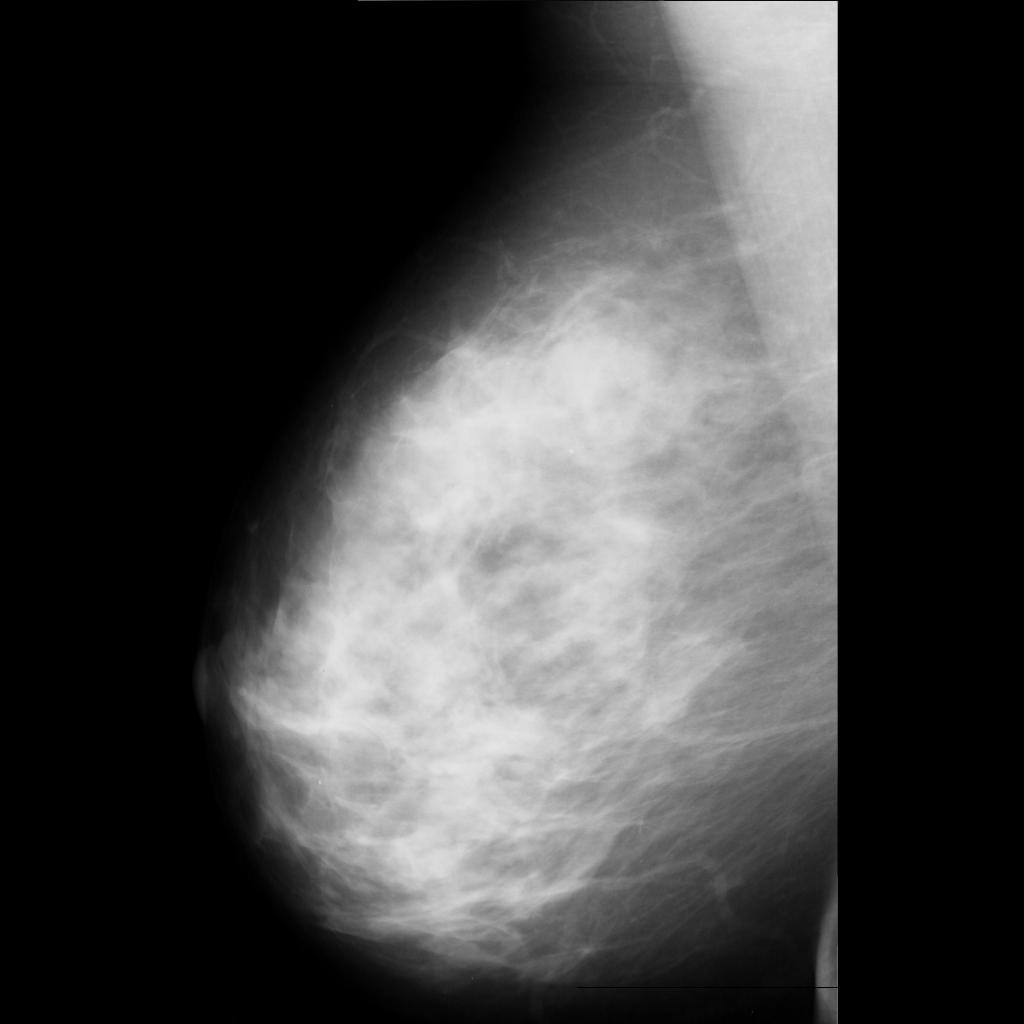

benign

malignant